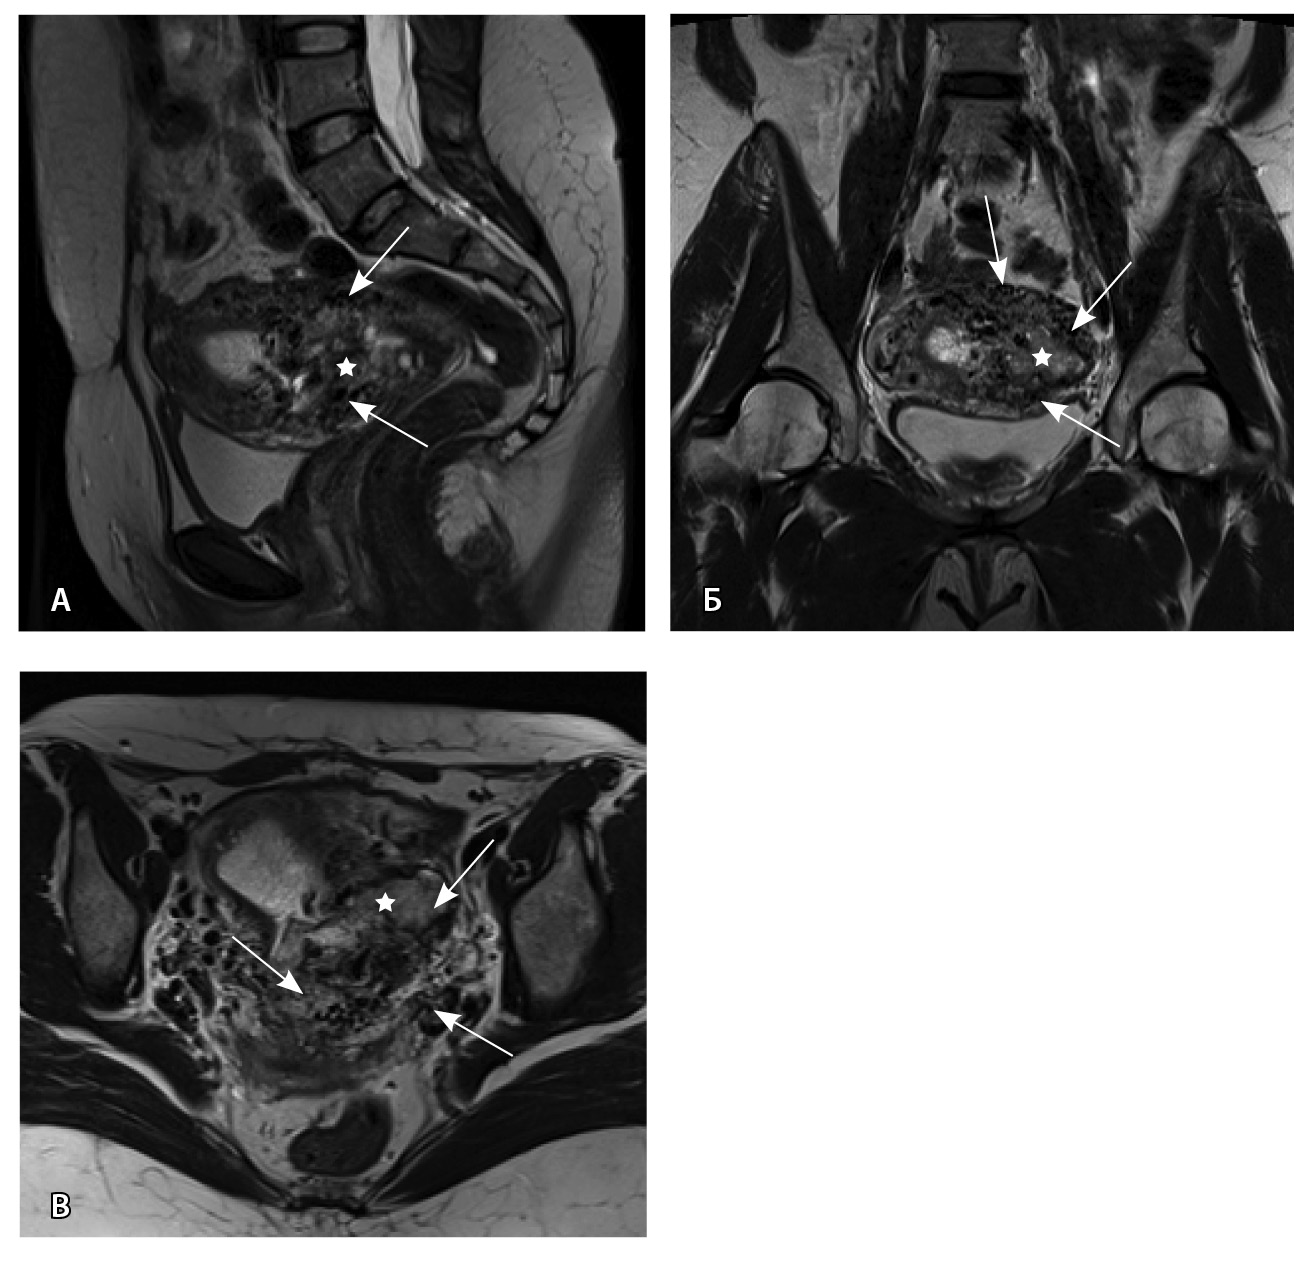

Пациентке выполнено МРТ-исследование на МР-томографе Siemens MAGNETOM Verio с индукцией магнитного поля 3T, с использованием стандартных катушек, в режимах Т1-взвешенного изображения (ВИ), Т2-ВИ, Т2-FS, FIESTA, DWI с получением изображений в сагиттальной, корональной и аксиальной плоскостях, динамическое внутривенное контрастирование (гадопентетовая кислота 0,2 мл/кг массы тела). Матка увеличена в размерах, с признаками снижения зональной дифференциации стенок, усиленным сосудистым компонентом, полость матки расширена с наличием примеси геморрагического содержимого, неравномерным утолщением эндометрия и пристеночными компонентами слизистой. В нижнем маточном сегменте определяется несостоятельный рубец от кесарева сечения, с наличием участка резко истонченной пролабирующей стенки матки слева и наличием дополнительного образования неоднородного сигнала, суммарно до 4,0 × 2,3 × 3,2 см, представленного фрагментами мягкотканного хориона (изоинтенсивного на Т2-ВИ), достигающего серозного покрова матки, и патологического сосудистого компонента в виде расширенных полнокровных сосудов, зон неоангиогенеза (рис. 1). На DWI признаков ограничения диффузии не определялось.

Рис. 1. Остатки вросшего хориона в несостоятельный рубец от кесарева сечения. Магнитно-резонансная томограмма, Т2-взвешенное изображение в сагиттальной (А), корональной (Б), аксиальной (В) плоскостях. Признаки наличия в проекции несостоятельного рубца от кесарева сечения фрагментов ткани вросшего хориона изоинтенсивного сигнала (отмечен звездочкой), с распространением до серозного покрова матки. Стрелками указаны гипоинтенсивные сосуды, зоны неоангиогенеза, артериовенозные сосудистые коллатерали

По наружной поверхности нижнего маточного сегмента и в параметрии определяется наличие полнокровной сосудистой сети с артериовенозными анастомозами. При контрастировании визуализируются фрагментарные участки гиперваскулярного накопления контраста вышеописанным образованием в рубцовой нише, а также определяется наличие артериовенозной сосудистой мальформации (рис. 2).